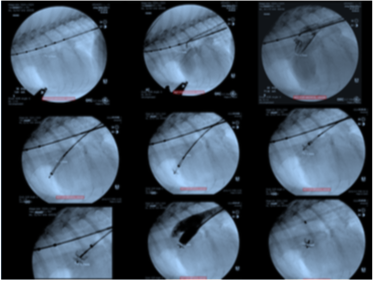

微創介入科

心臟胸腔科